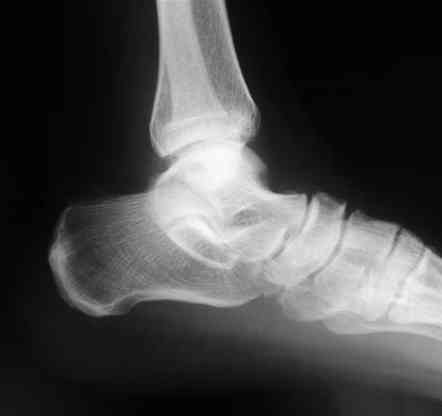

Лодыжку так ипрооперировал двумя 3.5 мм шурупами пришлось открыть - закрыто не удалось адекватно отрепонировать, при открытии - надкостничная

интерпозиция.

Бедро фиксировал длинной DCS.

В приложении отправляю послеопер. снимки бедра и лодыжки обсуждаемого вчера больного.